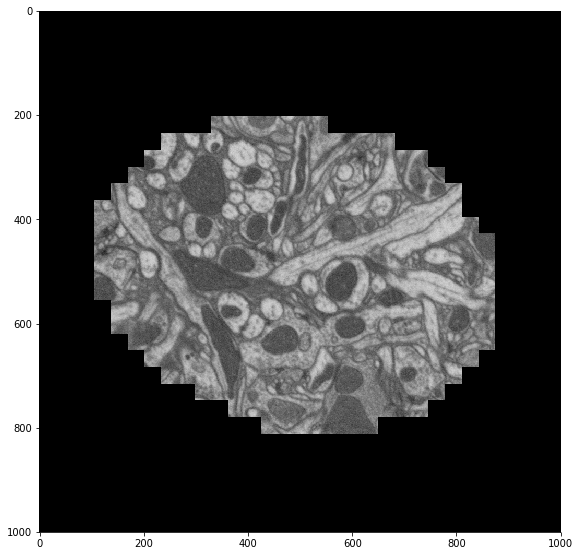

Recenter Images with Numba

In order to remove the spatial offset across time we’re going to compute a centroid for each slice and then crop the image around that center. I looked up centroids in the Scikit-Image docs and came across a function that did way more than what I was looking for, so I just quickly coded up a solution in Pure Python and then JIT-ed it with Numba (which makes this run at C-speeds).

>>> centroid(sample) # this takes around 9ms

(748.7325324581344, 802.4893005160851)

plt.figure(figsize=(8, 8))

skimage.io.imshow(recenter(sample))

Now we map this function across our distributed array.

We check our work by averaging our re-centered images across time and displaying that to the screen. We see that our images are better centered with each other as expected.

skimage.io.imshow(recentered.mean(axis=0))

This shows how easy it is to create fast in-memory code with Numba and then scale it out with Dask.array. The two projects complement each other nicely, giving us near-optimal performance with intuitive code across a cluster.